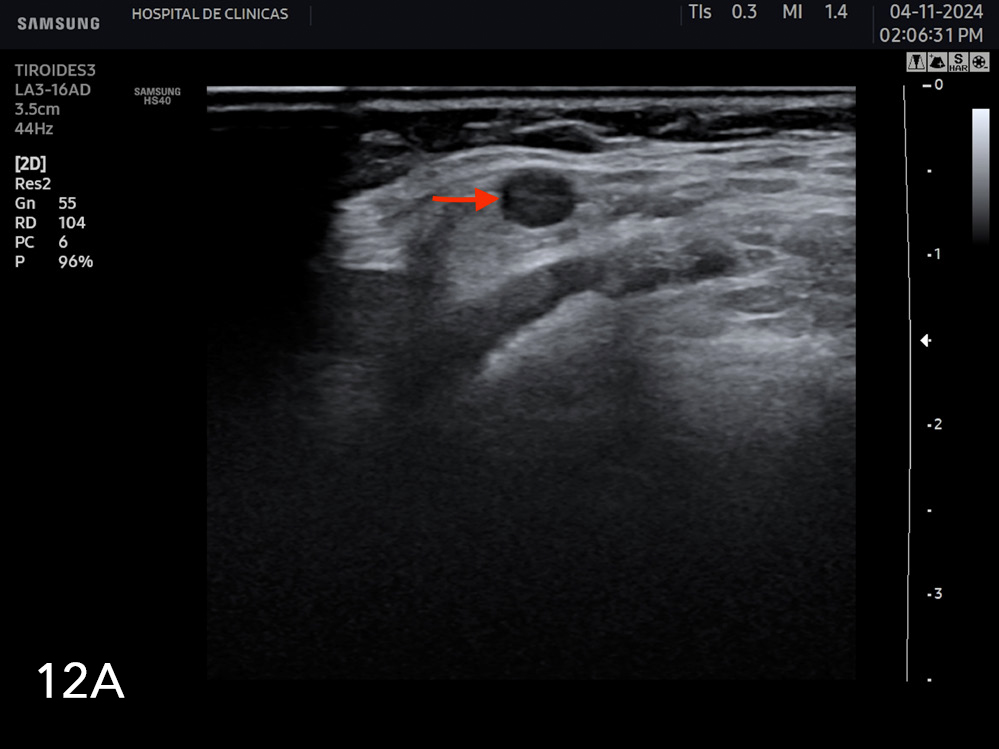

Se consideran características ultrasonográficas de adenopatías sospechosas de malignidad la quistificación, presencia de calcificaciones, pérdida de hilio graso, hiperecogenicidad, forma redondeada y vascularización anormal al Doppler. En la figura 12a y 12b se observan algunos ejemplos de adenopatías con características sospechosas de malignidad.